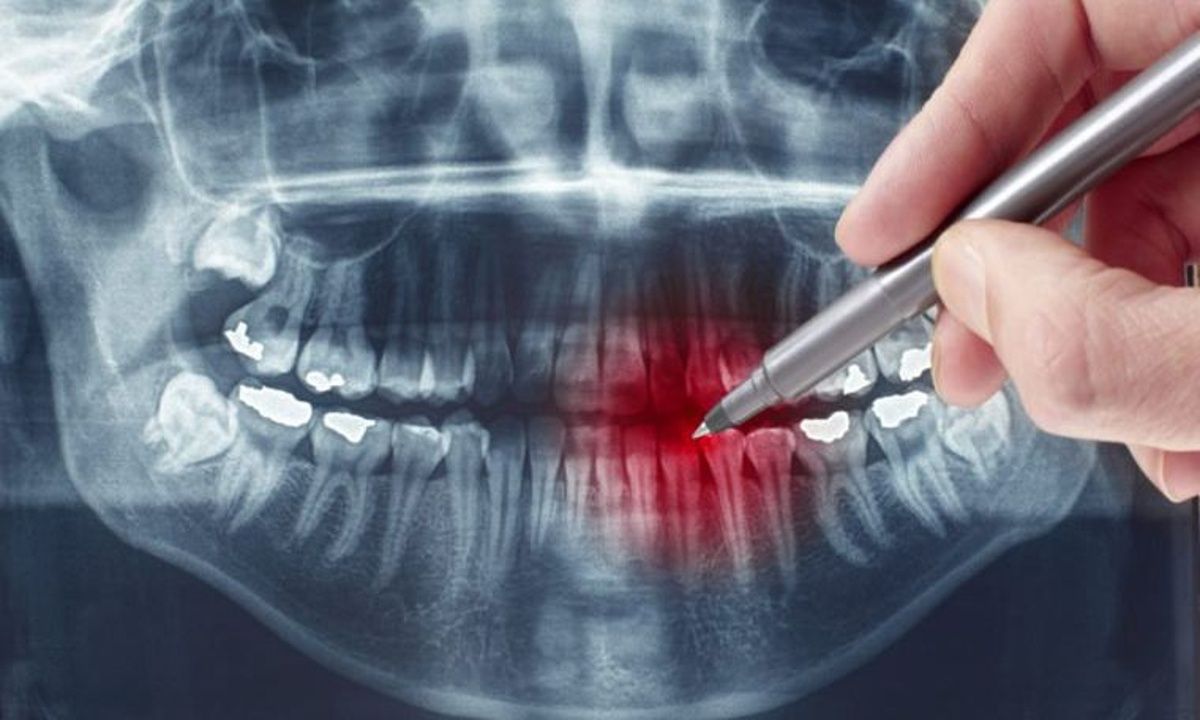

Αν αντιληφθείτε με τη γλώσσα σας κάτι αιχμηρό σε κάποιο δόντι, πρόκειται πιθανότατα για το πρώτο σημάδι μιας κοιλότητας, αποτέλεσμα φθοράς των δοντιών λόγω τερηδόνας.

Η τρύπα δεν έγινε μέσα σε μια νύχτα και το πιθανότερο είναι ότι η τερηδόνα «δουλεύει» μήνες στο στόμα σας.